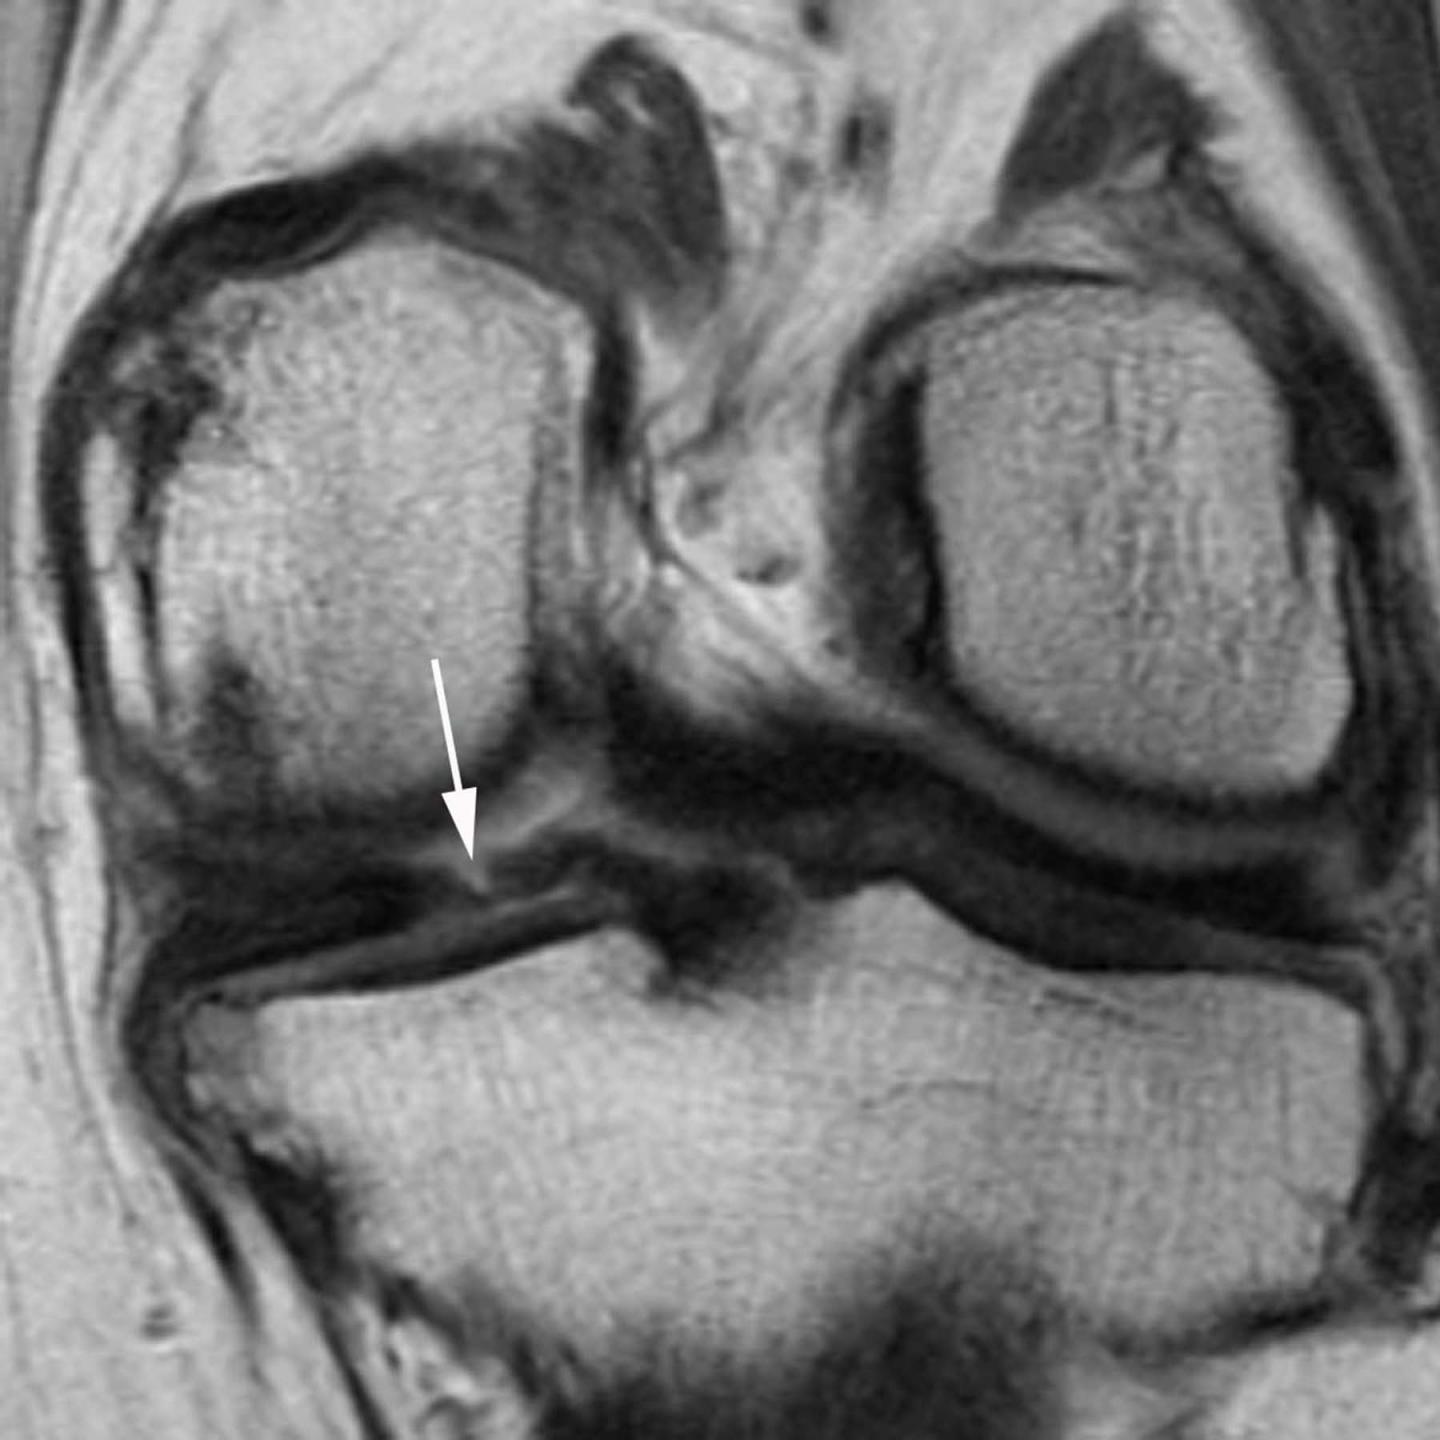

The new study focused on the meniscus, a wedge-shaped piece of cartilage in the knee that acts as a shock absorber between the femur, or thighbone, and tibia, or shinbone. The two menisci in each knee also play an important role in joint stability. Meniscal tears are among the most common knee injuries, and surgery is often performed to alleviate pain.

The researchers studied magnetic resonance imaging (MRI) exams of 355 knees that developed osteoarthritis during a five-year period, and a control group that was matched for age, gender, arthritic severity in both knees and BMI. Of all knees, 31 underwent meniscal surgery during the year prior to the arthritis diagnosis, and 280 knees had signs of meniscal damage on MRI but did not have surgery. Also part of the analysis were control cases with no meniscal damage. The researchers assessed the risk of developing arthritis and cartilage loss during the following year for the different groups.

All 31 of the knees that underwent meniscal surgery during the prior year developed osteoarthritis, compared with 165 (59 percent) of the knees with meniscal damage that didn't have surgery. In addition, cartilage loss was much more common among knees that had undergone surgery: 80.8 percent of knees with surgery showed cartilage loss, compared with 39.5 percent of knees with meniscal damage and no surgery.